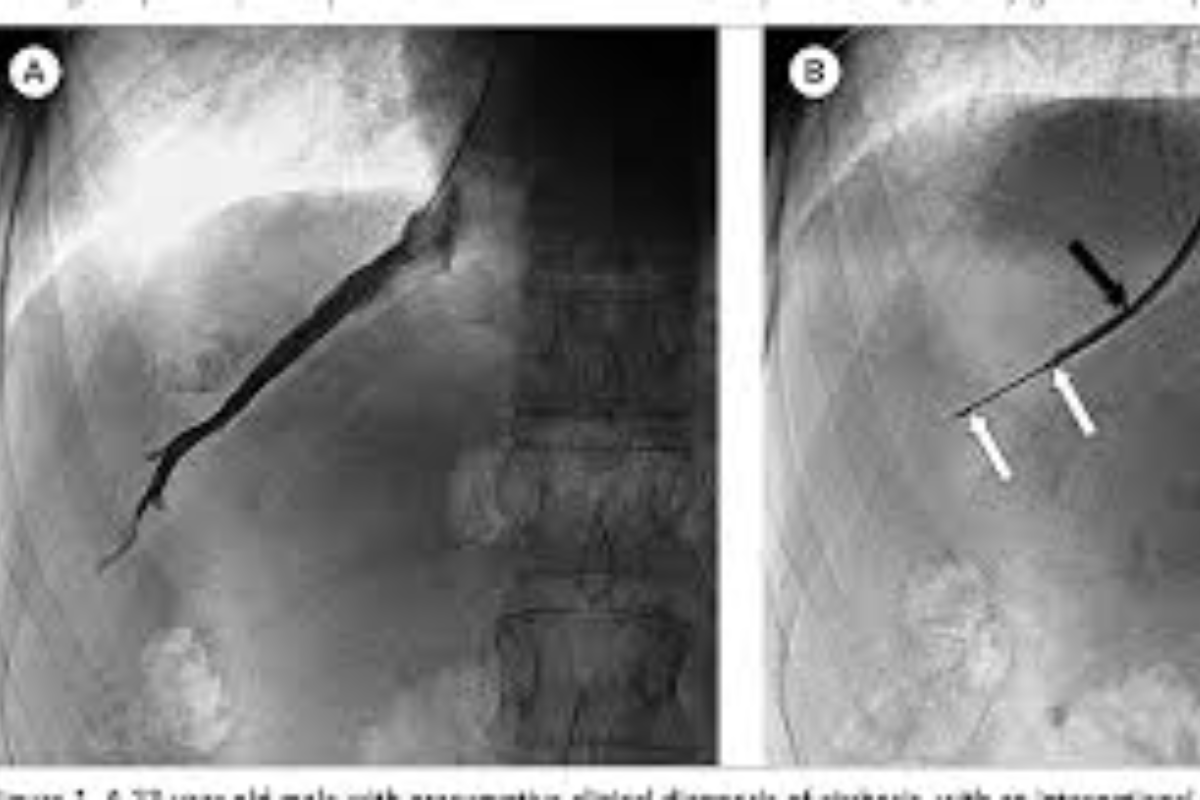

Peripheral Angioplasty procedure at Sarda Vascular Centre Dehradun

Interventional Radiology (IR) uses real-time imaging such as X-ray, ultrasound, CT, or MRI to guide tiny instruments through the body for treatment — without large surgical incisions.